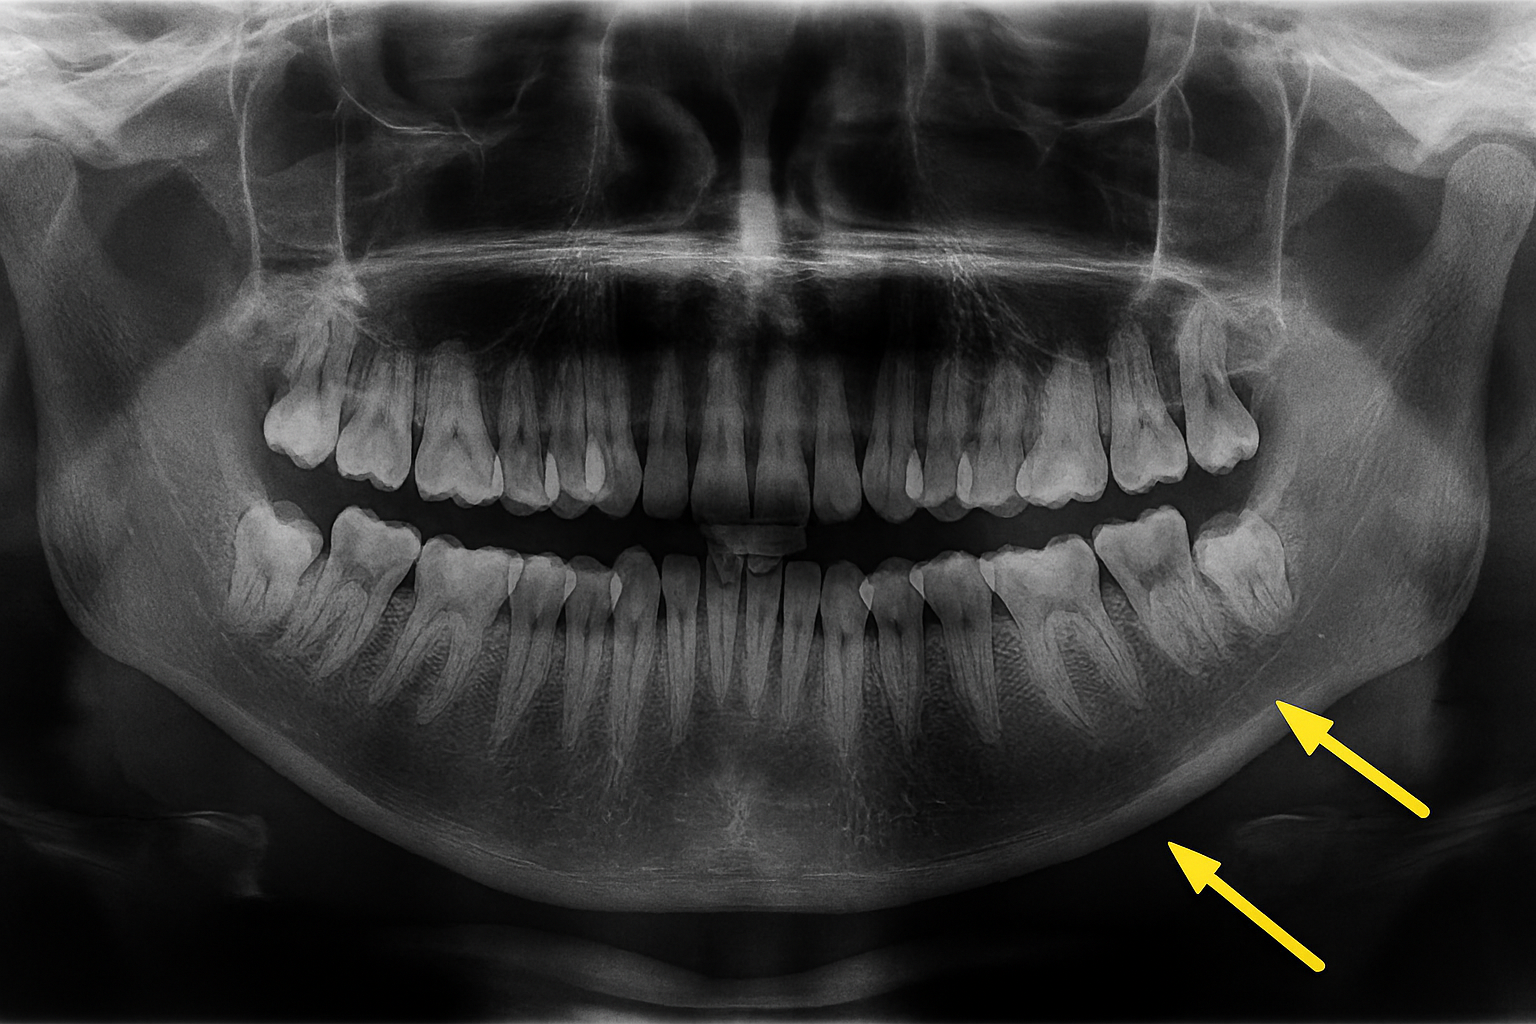

Raio-x panorâmico mostrando dentes do siso que podem precisar de extração.

A remoção de um dente, também conhecida como exodontia, pode ser necessária por diversos motivos, como cáries extensas que comprometeram a estrutura dental, doenças periodontais avançadas, dentes do siso (terceiros molares) mal posicionados ou por indicação para tratamentos ortodônticos.

• Diagnóstico Preciso: Utilizamos radiografias para avaliar a posição do dente e planejar a extração com máxima segurança.